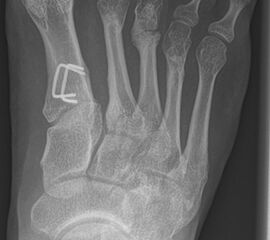

Schneiderballen: MT V Osteotomie

Diese Osteotomie ist indiziert bei stark lateralisierten MT V Köpfchen wie es nicht selten in Kombination mit einem Hallux valgus, einem Ballen-Hohlfuß oder Klumpfuß vorkommt (Abb. 25).

Dementsprechend führen wir die MT V Osteotomie häufig als Kombinationseingriff durch. Sie kann subcapital im Sinne der Kramer-Osteotomie oder adduzierend am Schaft durchgeführt werden (Abb. 26).

Abb. 26 a-e: adduzierende Osteotomie. (a) Fuß präoperativ d.p. und (b) als Schrägaufnahme. Im Schrägbild gut sichtbar die subluxierte 5. Zehe. (c) intraoperative Aufnahme der MT V Schaftosteotomie. (d) Fuß postoperativ d.p. und (e) als Schrägaufnahme.